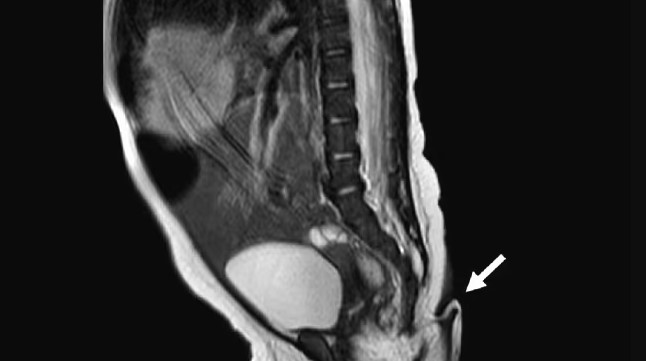

Рождение ребенка с таким атавистическим признаком, как хвост, крайне редкое явление. Медицине известно менее 200 подобных случаев